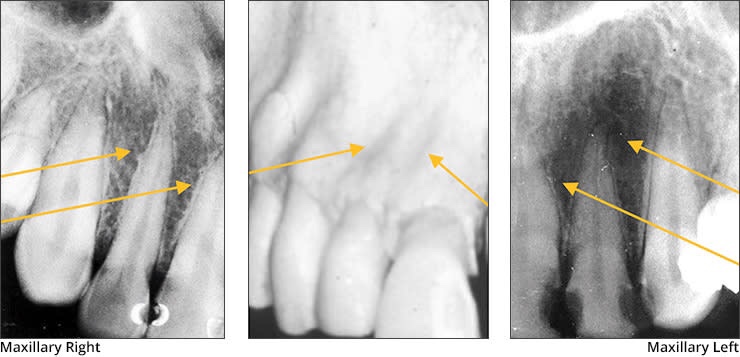

2) Maxillary Anterior landmarks:

• Nasal fossa – The nasal fossae are the nasal openings located above the maxillary anterior teeth. Radiographically, the nasal fossae appear as vertically oblong radiolucent structures bounded by bone.

• Anterior Nasal spine – Located at the anterior & inferior portion of Nasal cavity situated in the midline. Appears as a V-shaped or triangular radiopacity.

• Nose – Soft tissue tip of nose is seen in projection of maxillary central & lateral incisor. Appears with uniform opacity.

• Nasal Septum – Vertical bony wall that divides the nasal cavity into right & left fossae formed by Vomer & ethmoid bone.

• Inferior concha – Appears as diffuse radiopaque mass within nasal cavity.

• Intermaxillary suture – Immovable b/w two palatine process of maxilla.

• Nasal cavity – Pear shaped, air filled conpartment of bone located superior to maxilla, appears as radiolucent area.

• Incisive foramina – Nasopalatine vessels & nerves lies in midline on lingual aspect of hard palate. Radiographically, it appears between the roots of the central incisor teeth as a round to oval radiolucency less than one centimeter in diameter.

• Floor of nasal cavity – Bony wall formed by palatal process of Maxilla & horizontal portion of palatine bone. Appears as dense radio-opaque band that cuts the maxillary process.

• Lateral/canine fossa – Great depression in the maxilla in the region of apex of lateral incisor. Inferior to infra-orbital foramen b/w laterals & canines.

• Y line of Ennis – The inverted Y is a radiographic landmark that depicts where the nasal fossa crosses the maxillary sinus. The boundary between them is shaped like an upside-down letter Y, hence its name.